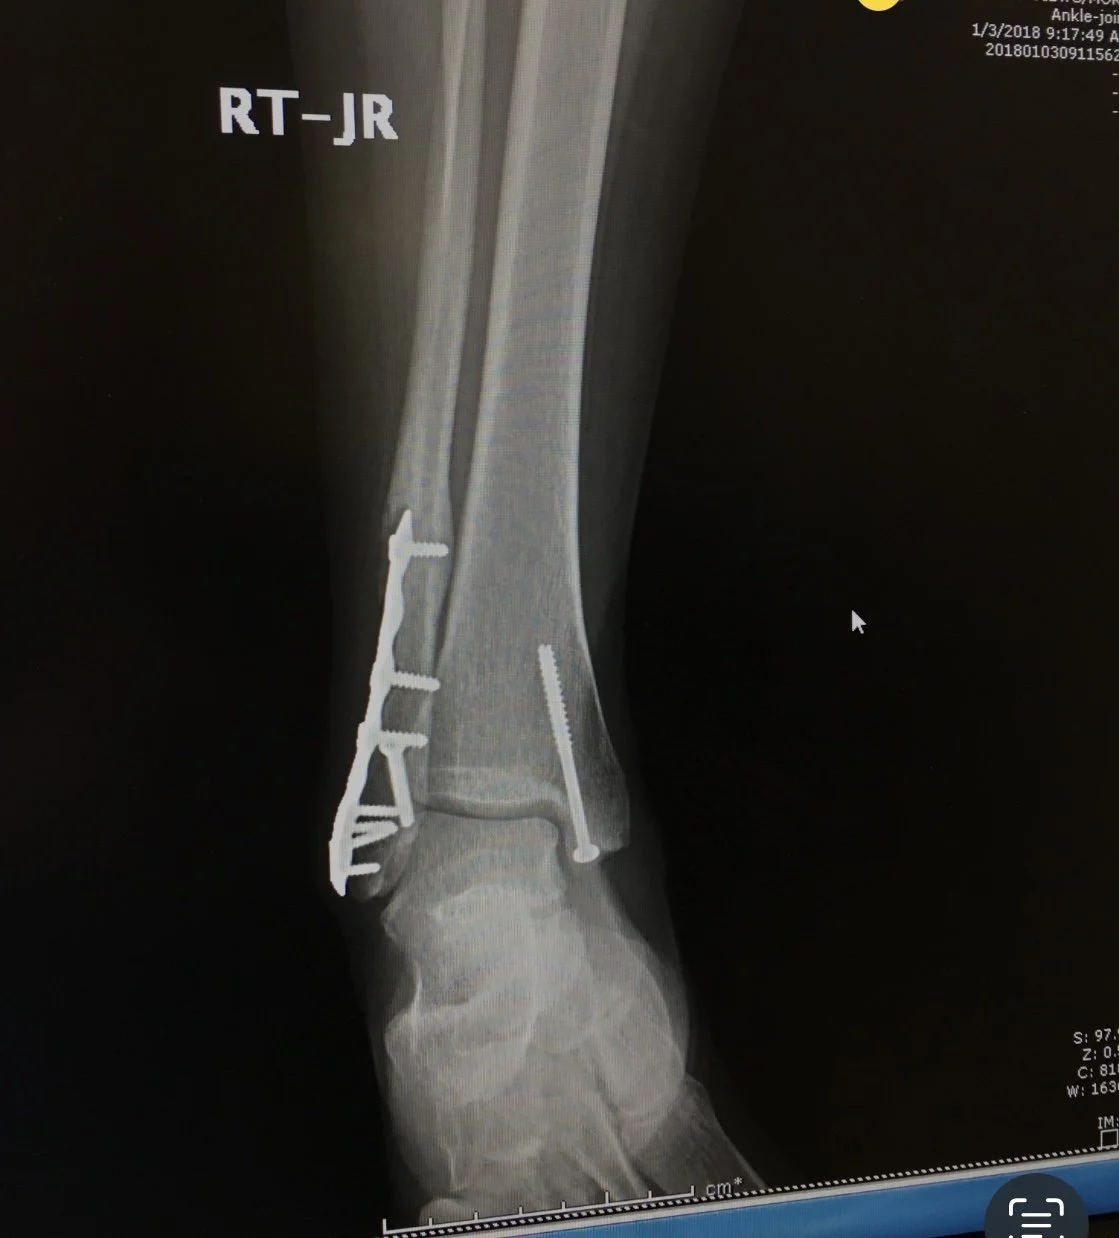

The orthopedic surgeon told me it would be 12 months before I could walk. Everyday following the surgery I practiced a Yoga Nidra Meditation. 6 months after the surgery I was walking. Shocked my surgeon asked what I was doing and I told him Yoga Nidra Meditation. He looked at me and said, “I got to tell my patients about this.”